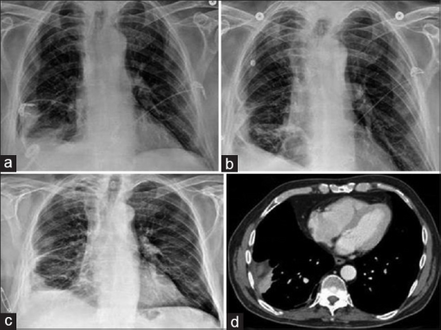

Progression of empyema

An empyema (/ˌɛmpˈmə/) is a collection of pus within a naturally existing anatomical cavity. For example, pleural empyema is empyema of the pleural cavity. It must be differentiated from an abscess, which is a collection of pus in a newly formed cavity. The term is from Greek ἐμπύημα, "abscess".

Lungs[edit | edit source]